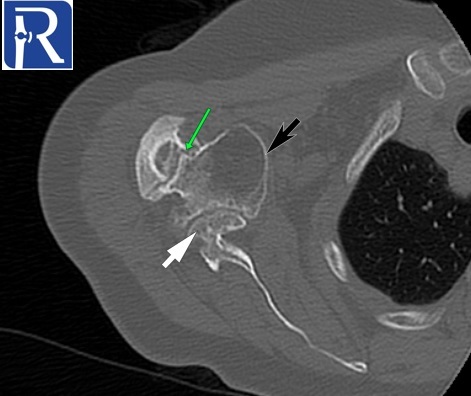

Demographic and clinical details: 70-years-old female patient, admitted with right shoulder pain and restricted motion.

Image Details: AP X Ray shows the inferior glenohumeral joint dislocation with non-united neck fracture (yellow arrow=. Note also deformation of humerus head (black arrow) and glenoid (white arrow). You can notice also superior cortical compression of humerus head consistent with hill sachs lesion. These findings are better seen on CT images.